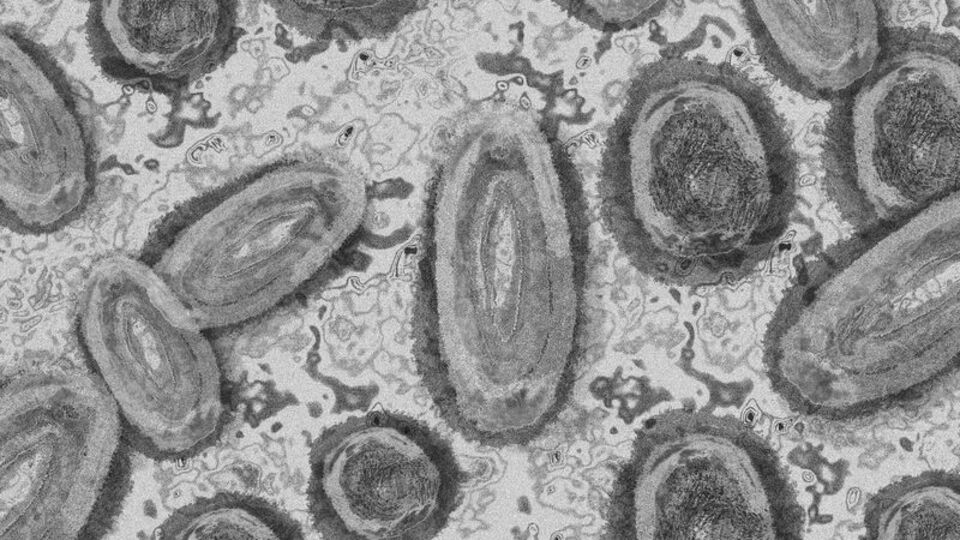

Pekin’de maymun çiçeği virüsü nedeniyle 2 kişi karantinaya alındı

Dünya genelinde endişelere neden olan maymun çiçeği virüsü Çin'in başkenti Pekin'de görüldü. Pekin Hastalık Önleme ve Kontrol Merkezi tarafından yapılan açıklamada, yurt dışı kaynaklı bir vaka görüldüğü ve bu vakayla temaslı bir kişide daha virüs tespit edildiği belirtildi

Orta ve Batı Afrika ülkelerinde yaygın olarak görülen maymun çiçeği virüsü şuana kadar 111 ülkede tespit edildi. Dünya Sağlık Örgütü (DSÖ) tarafından 11 Mayıs’ta yapılan açıklamada, maymun çiçeği virüsünün yüzde 90 oranında azaldığı ve artık uluslararası öneme sahip bir halk sağlığı acil durumu olmaktan çıkarıldığı ifade edilmişti.